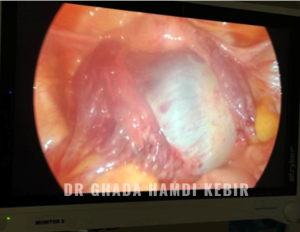

Le traitement chirurgical consiste souvent en une coelioscopie sous anésthesie générale afin de retirer la grossesse ectopique tout en gardant la trompe (traitement conservateur) ou en retirant la trompe (traitement radical).

Rarement le médecin est amené à pratiquer une laparotomie surtout en cas de problèmes hémodynamiques de la patiente ou insuffisance du plateau technique.